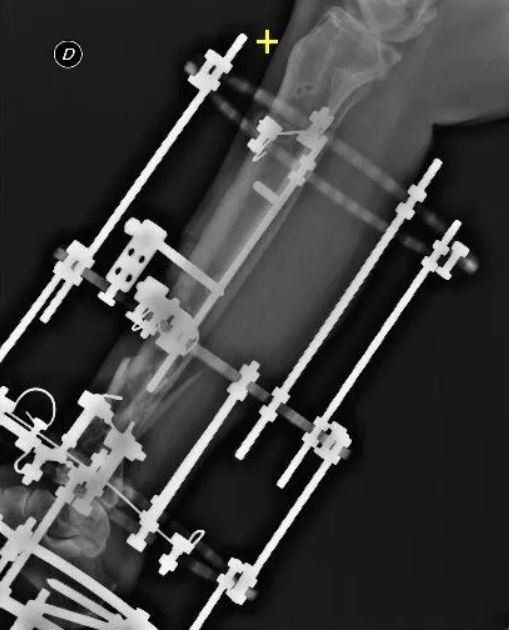

- External fixation: Orthopaedic surgeons apply an external device to the affected limb using steel wires and pins. This method is preferred for pseudoarthrosis without sufficient stability, infected cases, or those with bone loss.

Recent technical innovations have led to the development of more advanced external fixators that allow axial correction of deformities and bone healing, utilising osteogenic distraction. These fixators, called Hexapods, have transformed external fixation, making it simpler and easier for patients to manage. By gradually changing the length of 6-millimetre rods, the patient can autonomously correct axial deviations and lengthen the bone segment if necessary.